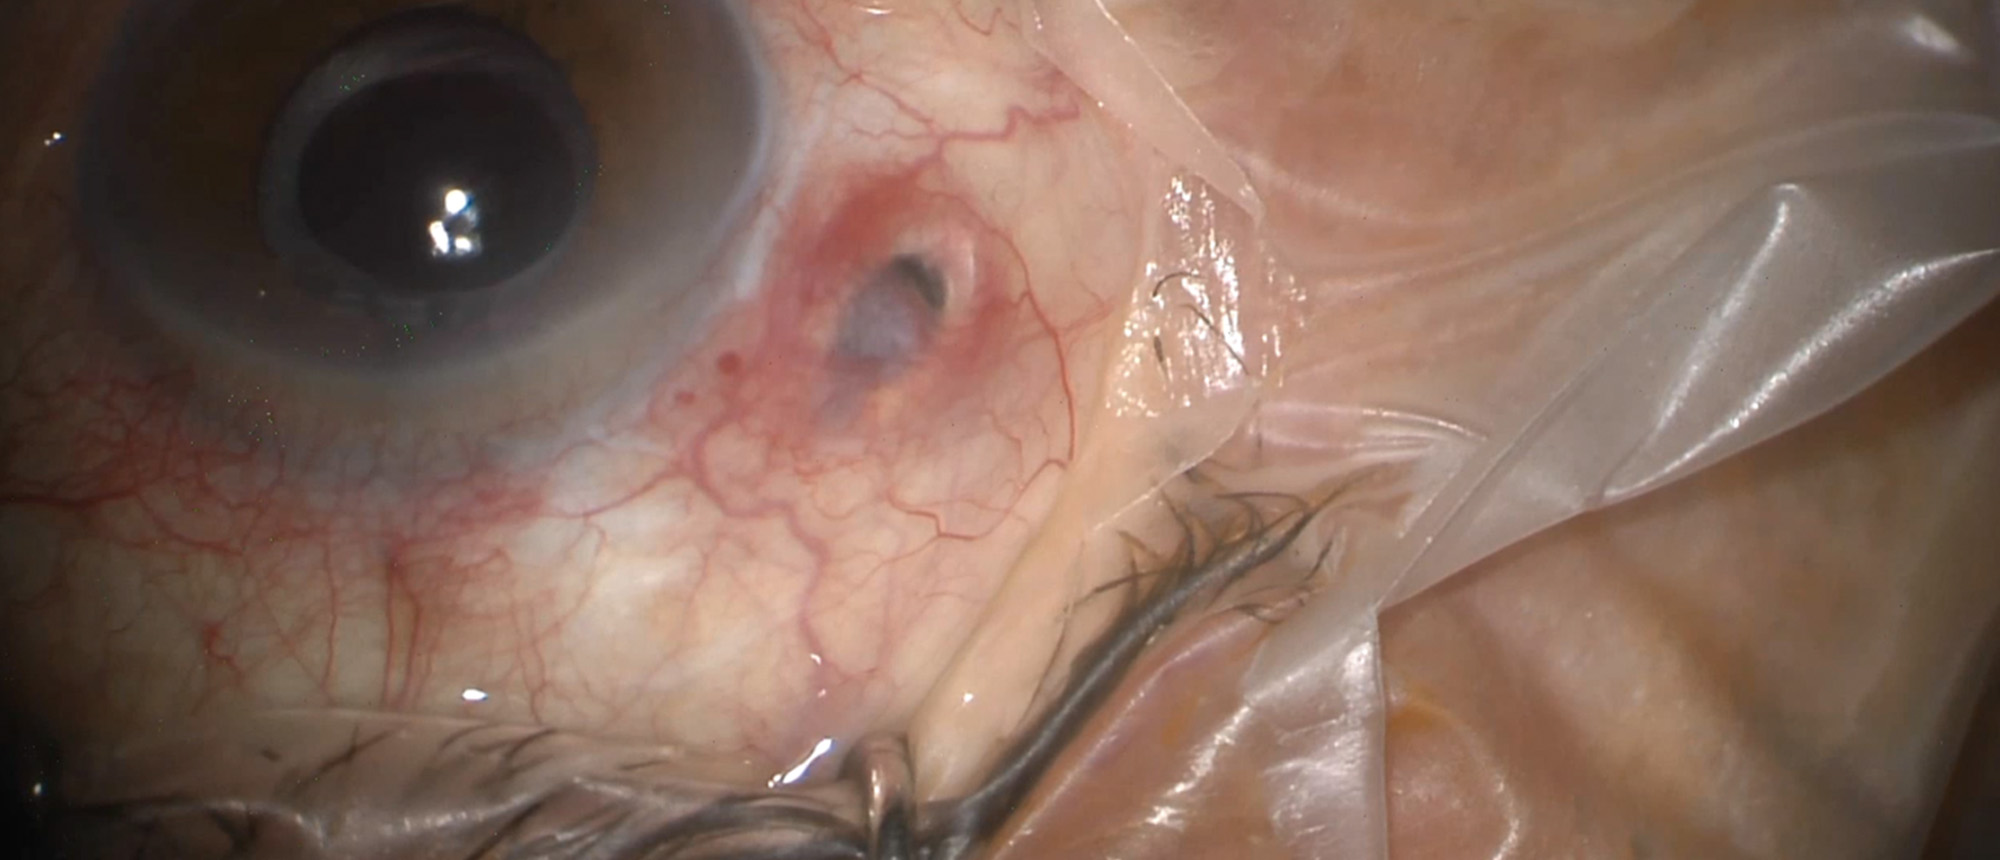

Diabetes Managed with Anterior Chamber Islet Cell Transplant A patient with past medical history of uncontrolled diabetes and open globe injury of the right eye presents with blurred vision in her left eye. She had LP vision in her right eye. Her examination demonstrated changes consistent with pri…